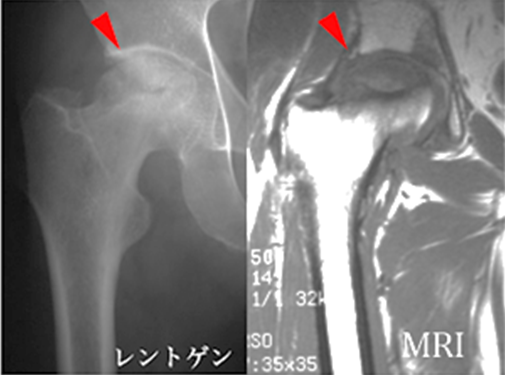

図5. 大腿骨頭壊死症

(赤矢印が骨頭壊死部分)

5. 大腿骨頭壊死症

大腿骨頭壊死症は、大腿骨頭への血流障害によって股関節が破壊される病気で(図9赤矢印)原因は分かっておらず難病指定されています。しかし、ステロイド剤を多量に使用したパルス療法やアルコール多飲歴の有る方に多く発症しやすい傾向があります。

- 大腿骨頭への血流障害によって股関節が破壊される病気

- 原因不明

- ステロイド剤を多量に使用した場合やアルコール摂取量の多い人に発症することが多い

図9. 代替骨頭壊死症(赤矢印が壊死部分)